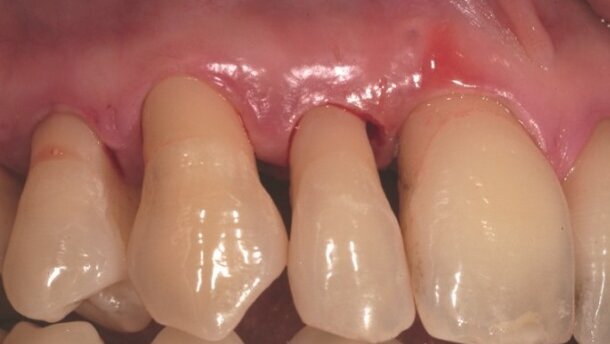

Mając na uwadze konsekwencje biologiczne i stosunek ryzyko-korzyść, wykonanie inwazyjnego zabiegu nie wydaje się obecnie najkorzystniejszą formą terapii (Heitz-Mayfield i Land, 2013, Walsh i Waite, 1978; Badersten et al., 1984a, 1984b; Leon i Vogel, 1987, Oosterwaal et al., 1987; Cobb, 1996). Nasza wiedza w dziedzinie mikrobiologii i immunologii rozwinęła się tak samo, jak wykorzystanie nowoczesnych urządzeń terapeutycznych. Dzięki temu, dysponujemy technologiami umożliwiającymi stosowanie alternatywnych procedur i terapii w leczeniu chorób przyzębia. Laser Er:YAG może być ważnym elementem tej strategii (Ryc. 4-6).

Laser Er:YAG we wstępnym leczeniu przyzębia

Laser Er:YAG może być użyty do uzupełnienia lub nawet zastąpienia konwencjonalnych narzędzi w chirurgicznych lub niechirurgicznych procedurach terapeutycznych. Jak udało się zaobserwować, jego biologiczne efekty umożliwiają mu działanie jako wysoce selektywnemu i przez to bardzo precyzyjnemu narzędziu optycznemu, które spełnia nieinwazyjne kryteria przy usuwaniu tkanki w stanie zapalnym. Jego działanie antyseptyczne jest używane do czyszczenia korzeni i powierzchni kości poprzez bezpośrednią zastosowanie w miejscach zapalnych (Yoshino, 2009).

Ergonomiczny kształt włókna lasera sprawia, że jest to bardzo dobre narzędzie, które może być używane do leczenia obszarów, które są często niedostępne dla konwencjonalnych narzędzi (Sahar-Helft & Stabholtz, 2013). Z uwagi na procesy zjawisk fotomechanicznych (mikroeksplozje i fale wstrząsowe), efekt antyseptyczny lasera Er:YAG jest potwierdzony badaniami klinicznymi i wpływa również na obszary poza tymi, które są dostępne przez bezpośrednie promieniowanie. Laser Er:YAG jest prawdziwym narzędziem chirurgicznym, ale z uwagi na swoją ekstremalną precyzję, osiąga pełen potencjał, kiedy jest używany w minimalnie inwazyjnych lub niechirurgicznych terapiach i zastosowaniach sprzyjających gojeniu (Schwarz, 2007).